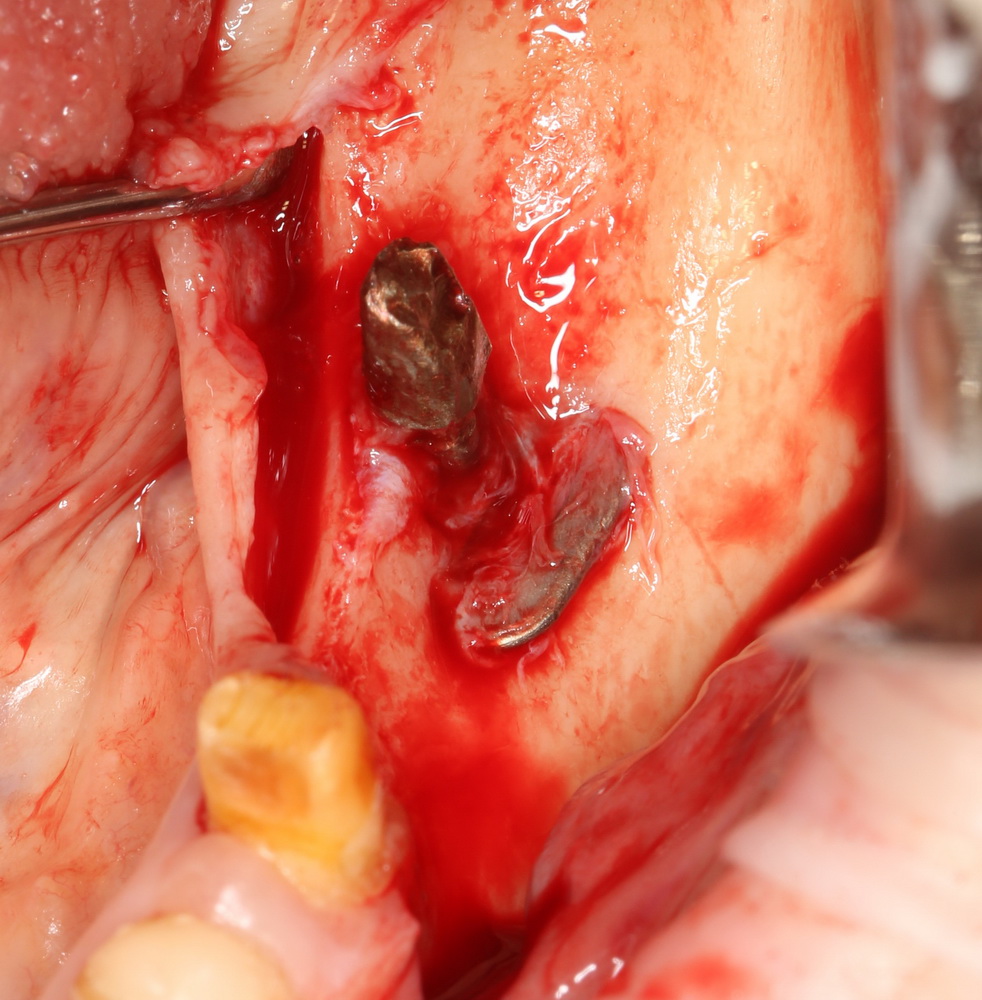

и, периодически, мне приходится видеть пациентов с базальными имплантами:

Как правило, вся работа с этими имплантами сводится к их удалению:

Затем — восстановление утраченных объемов костной ткани и нормальная, винтовая имплантация.

И вот, у этой пациентки все импланты, а их, ни много, ни мало, восемь штук, подвижны:

Мы вынуждены их удалить. И теперь представьте, как будет проходить такое удаление и с каким дефицитом костной ткани мы, в итоге столкнемся. Что вообще делать дальше? Девушка плачет.